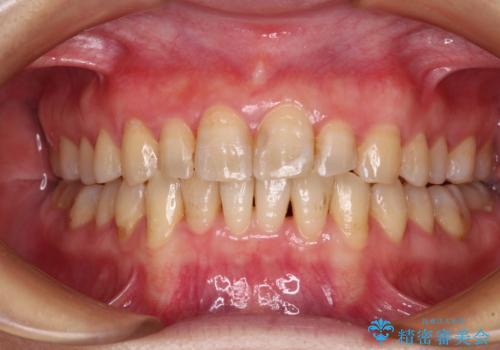

- 前歯のデコボコを治したいとのことで来院された患者様です。

上下顎ともに歯列全体の後方移動とIPR(歯と歯の間を削る)によってデコボコが解消するように設計し、インビザラインにより治療を行うこととしました。